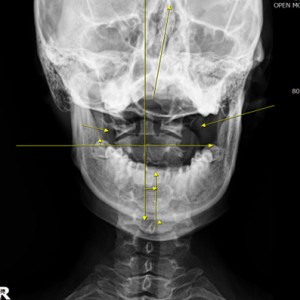

안면 두개골 엑스레이 검사

Submento Vertex View 포함

경추 1,2번의 변위 파악

안면 균형검사

턱의 다양한 각도 사진 촬영